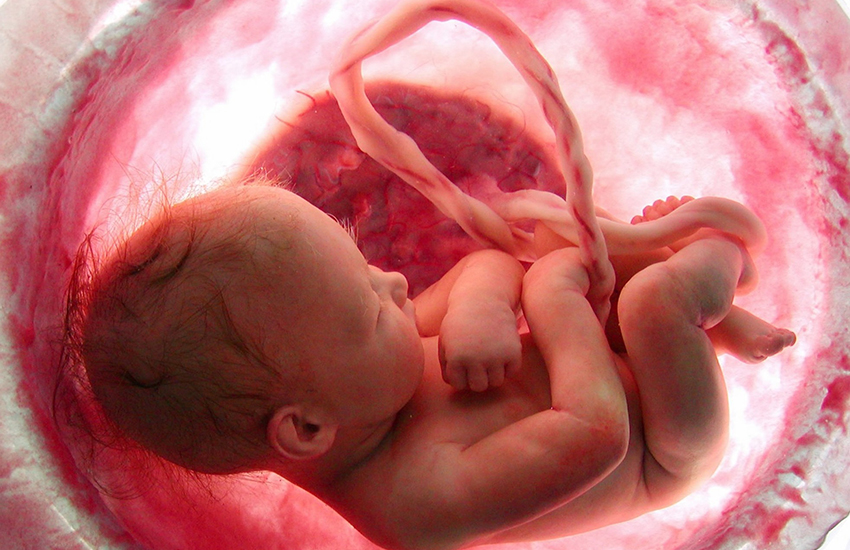

Göbek kordonu, bir fetüsü annenin plasentasına bağlayan, oksijen ve besin açısından zengin kan sağlayan ve atıkları uzaklaştıran tüp benzeri bir yapıdır.

Göbek kordonunun bir ucu bebeğin eşi olarak da bilinen plasentaya, diğer ucu ise bebeğin göbeğine bağlıdır. Annenin vücudu ile bebek arasında iletimi sağlar.

Tüm insanlarda bulunan göbek deliği, bir zamanlar göbek kordonu olarak adlandırılan çok önemli bir anatomik yapı için giriş noktasıdır. Göbek kordonu, oksijenli kanı ve besinleri plasentadan fetüse, karnın içinden geçerek taşır.

Ayrıca fetüsten plasentaya oksijensiz kan ve atık ürünleri taşır. Bebek doğduğunda, göbek bağı bebeğin vücuduna yakın kesilir ve kuruduktan sonra kendi kendine düşer.